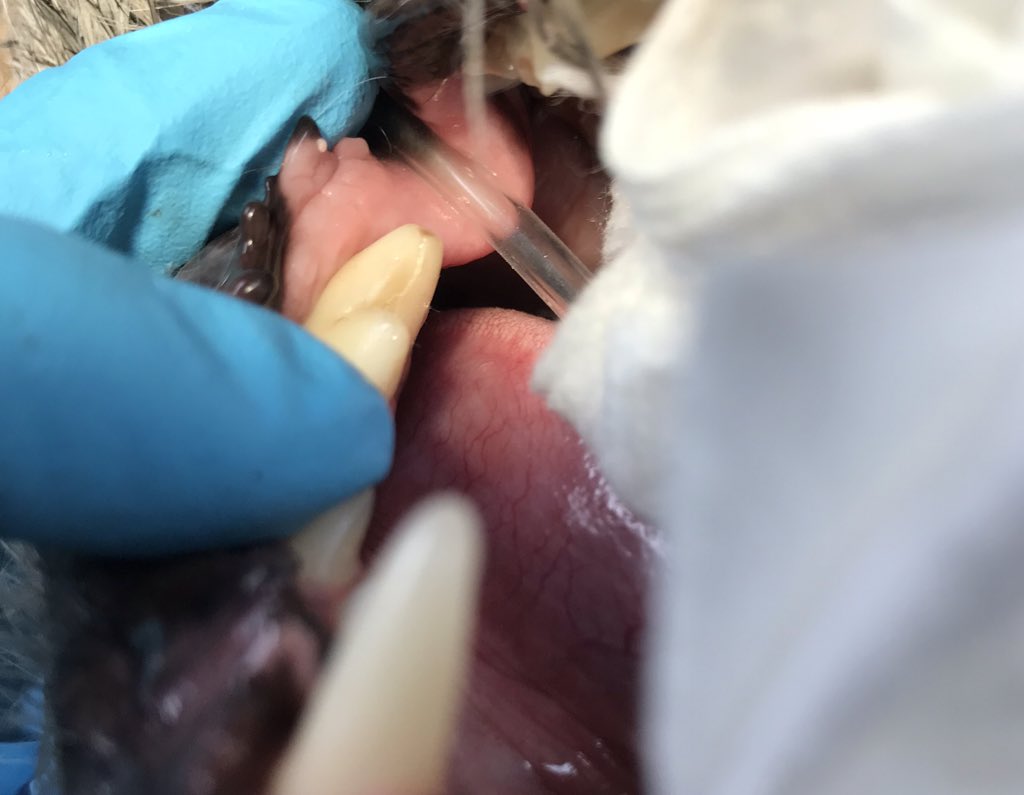

Interesting #dental case #2: same dog, this is his opposite tooth. Also has #periapical lysis. This shows the importance of #FullMouthXrays